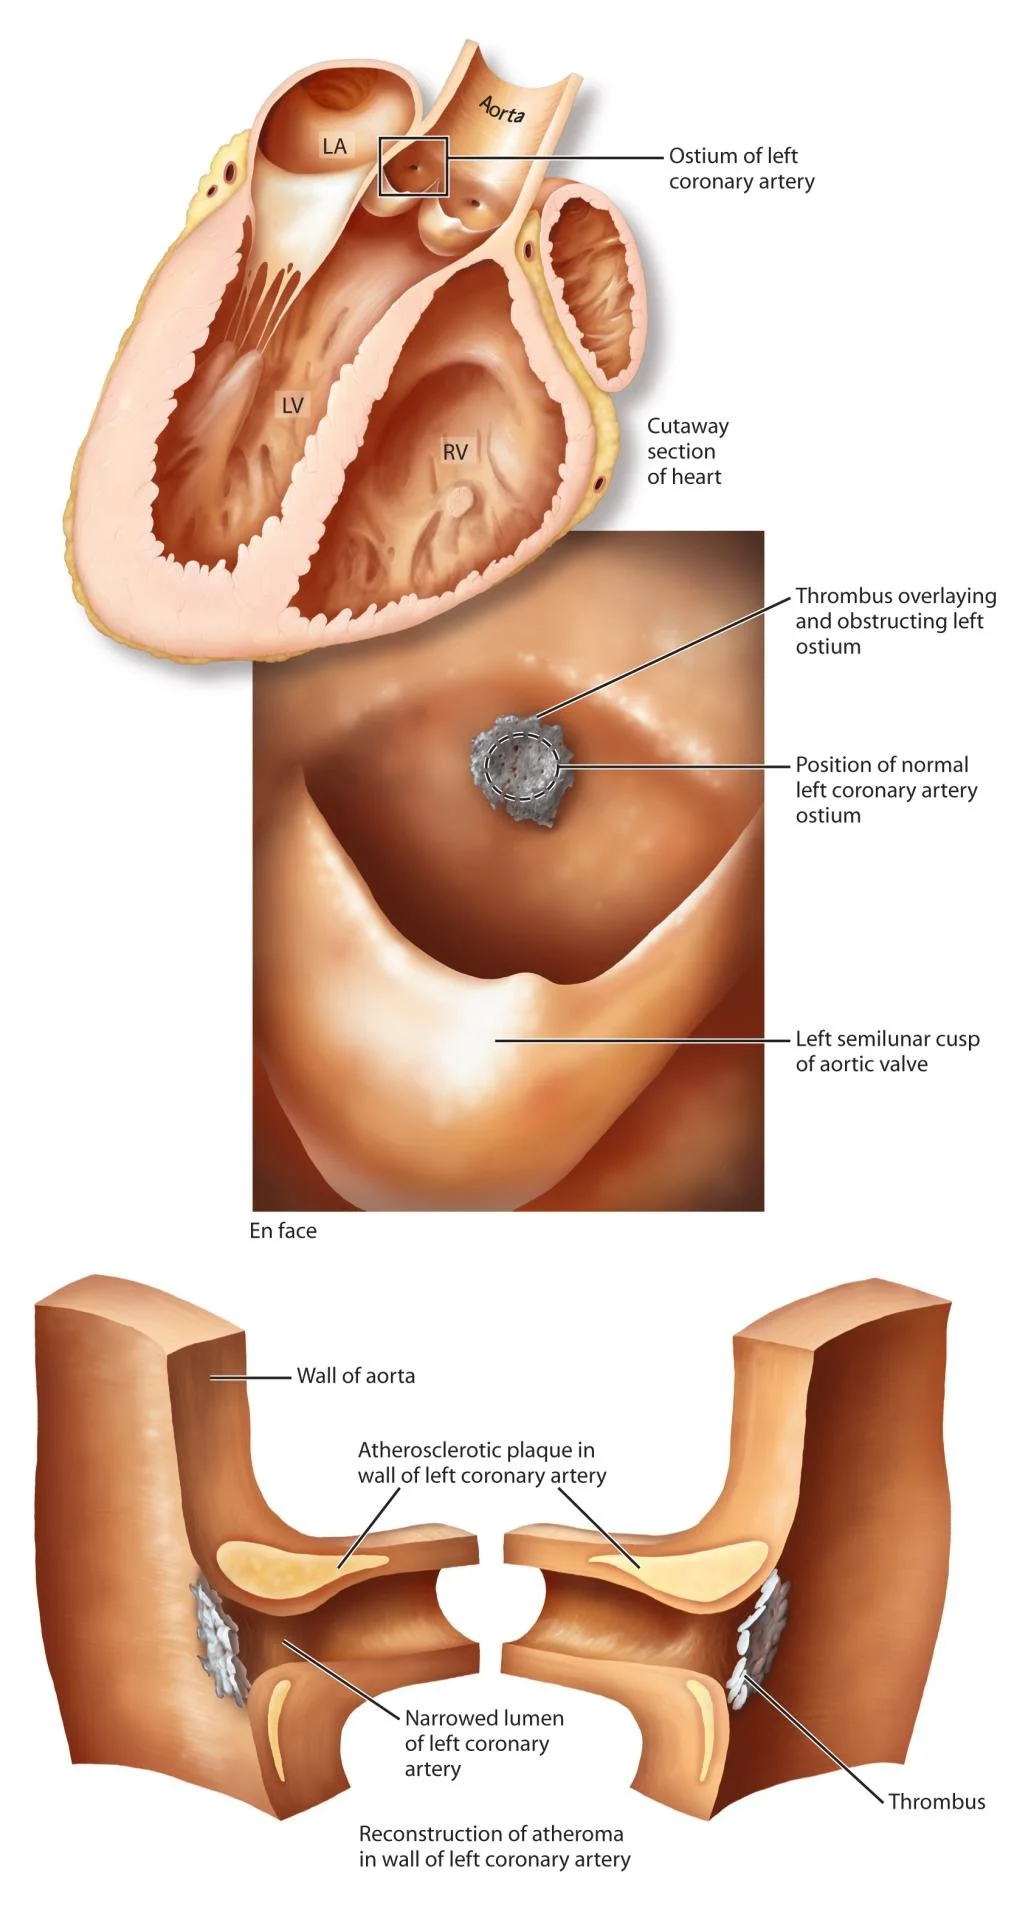

Medical Illustration

All images are works made for hire and are the exclusive property of the client. These are shown as sample purposes of my work only. For licensable work, please see my Illustration Services page.

Medical Illustrator for Precision Graphics, Lachina, and Human Kinetics Publishing (current)

Contract freelancer for many others, some examples of my work below.